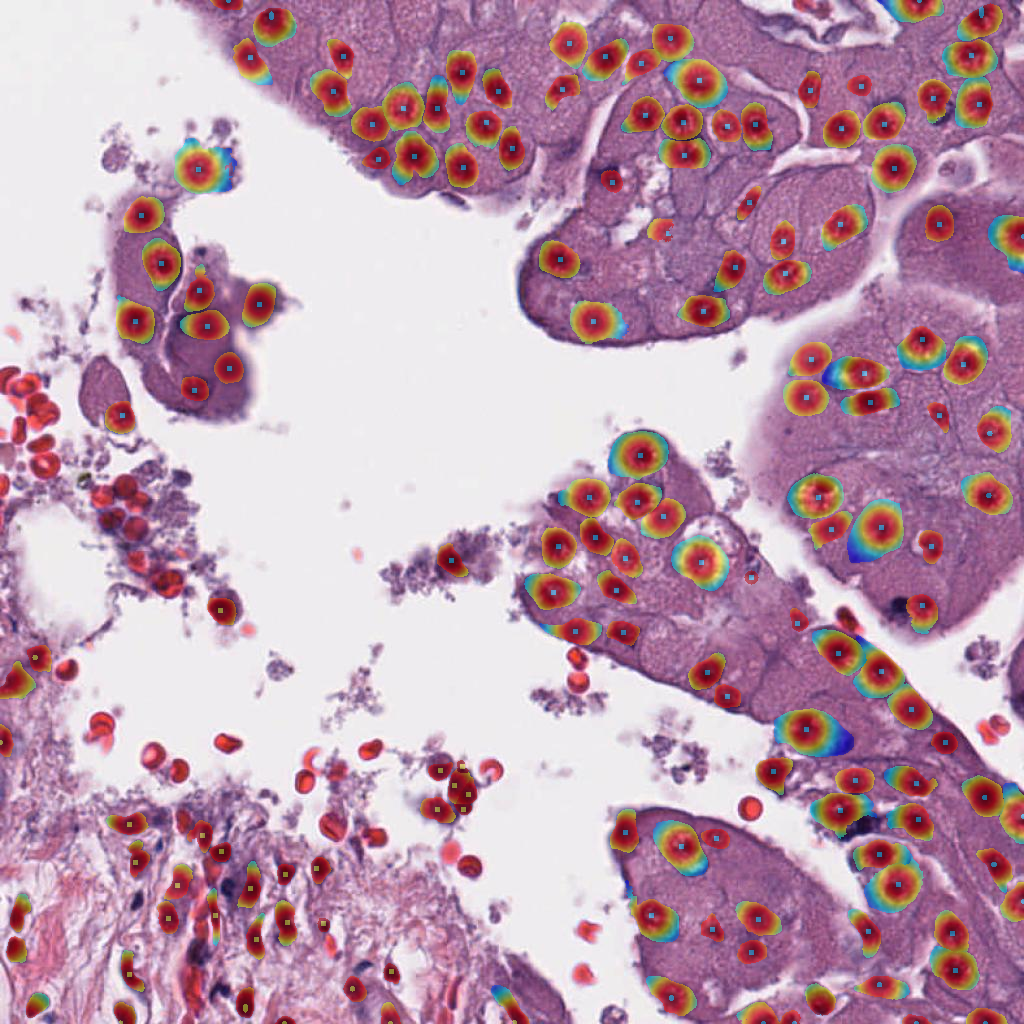

For the circle and soft IS ground truth formats we extract cell detection candidates from the segmentation prediction by applying skimage.feature.peak_local_max on the blurred foreground prediction (Figure 3), where:

and are the model predictions for the tumor cell class and background cell class respectively. Only cell candidates with a larger probability for the tumor or background cell class, compared to the background class, are considered. The cell candidate class is assigned as the foreground class with the highest probability. The hard IS requires a different approach, as cell instances are not trained to express a peak at the cell center and tend to overlap. For this reason, markers are extracted from the foreground prediction and then applied in a marker-controlled watershed segmentation to separate touching instance (more details in Appendix 0.B). The cell is assigned a class by majority vote of its pixel class predictions.

Appendix 0.A Segmentation ground truth generation with NuClick

We utilize NuClick [1], a pretrained nucleus, cell and gland segmentation model444Publicly available at https://github.com/navidstuv/NuClick, last accessed 24.11.2023, to extend the cell annotations from centroid coordinates to segmentation maps, as visualized in Figure 5. It relies on a guiding signal, in our case the cell point annotations, together with the input image for instance segmentation. Pretrained weights are only available for nuclei segmentation555https://drive.google.com/file/d/1MGjZs_-2Xo1W9NZqbq_5XLP-VbIo-ltA/view, last accessed: 24.11.2023, for this reason we extend the ground truth to a nuclei segmentation mask instead of a cell segmentation mask.